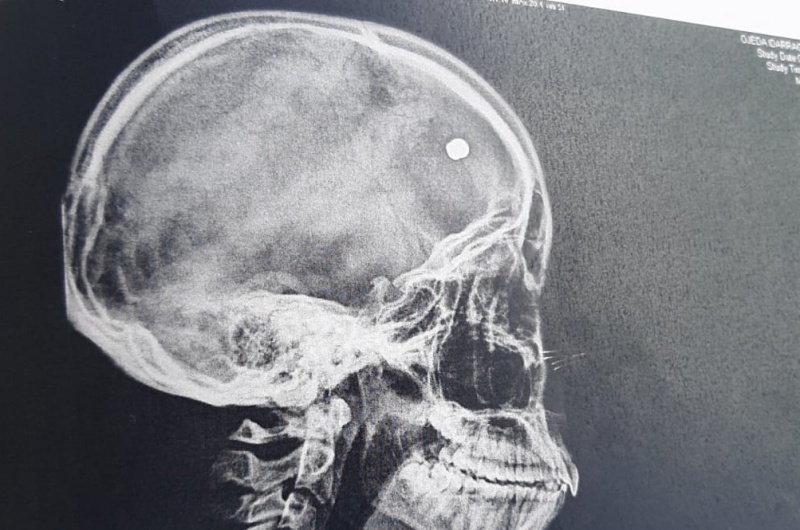

La mujer, vecina de Tías, ha denunciado que la niña iba por la calle y sintió un pitido agudo y luego un dolor muy fuerte en la cabeza. “Mi hija se cayó al suelo del dolor y se asustó muchísimo al ver la cantidad de sangre que le estaba saliendo de la cabeza. Cuando vino, con su sensey, que fue quien la trajo, la llevamos a Urgencias inmediatamente y de allí al hospital. Al hacerle las radiografías y un escáner detectaron que tenía un balín”, explica. “Al parecer le entró por un lateral de la cabeza y se alojó a unos seis centímetros, dentro del cuero cabelludo”.

A la niña le han podido quitar el balín y se encuentra bien, aunque asustada e impactada. “Hemos denunciado los hechos y parece que hay un señor que vive por la zona y ya ha disparado balines en otros momentos. Mató a un gato y le disparó al cristal de un coche por aparcar delante de la casa. Me parece surrealista que alguien en plena tarde empiece a disparar en un pueblo muy transitado y más hiriendo a una menor”, señala Vanesa que todavía no da crédito. “Espero que se tomen las medidas oportunas para que algo así no vuelva a pasar nunca”.